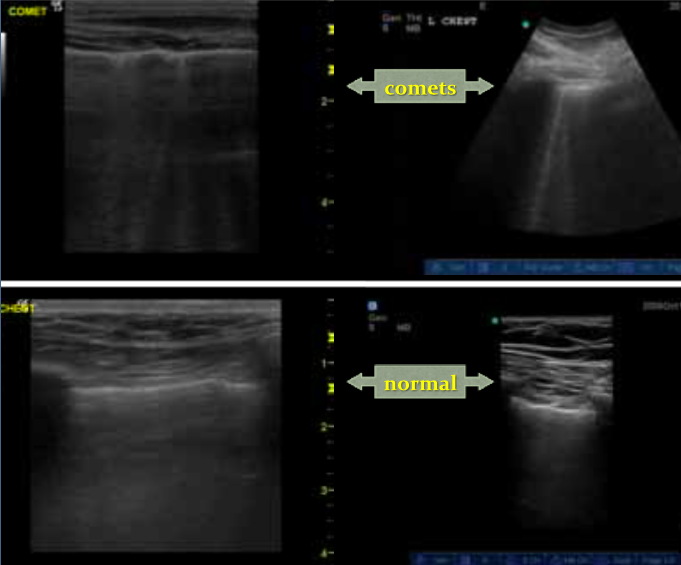

How do you tell if someone has pneumonia or CHF?

Look for comet-tails (vertical B lines as opposed to horizontal A lines which are normal). This is because the ultrasound penetrates the fluid better and comes back like multiple foggy headlights in the morning.